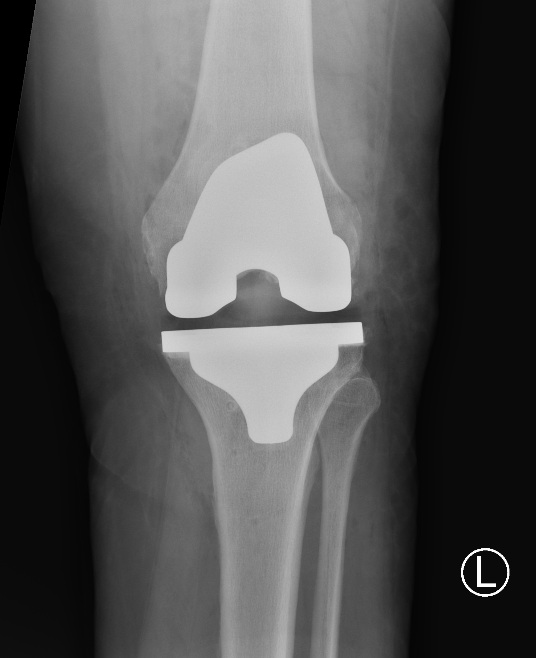

Example of Total Knee Replacement

Front on view of a total knee replacement